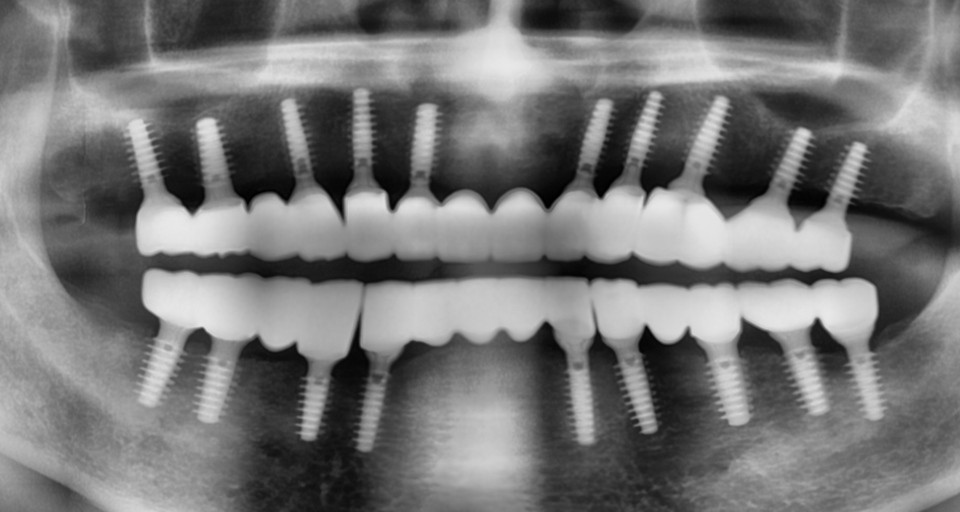

치료계획으로 의치에 대한 환자의 거부감과 양호한 치조골 상태를 고려하여 상악에는 10개, 하악에는 8개의 MagiCore 임플란트를 식립하여 치료하는 임플란트 지지 고정성 보철을 선택하였다.

CBCT를 촬영하여 식립 예정부위의 치조골 상태와 식립 방향을 분석하여 flapless 시술법으로 상악에 10개, 하악에는 좌측 견치의 발치 즉시 식립을 포함하여 8개의 MagiCore를 2일에 걸쳐 식립하였다 [그림 3~4].

수술 10일 후 다소 근심으로 식립된 하악 좌측 제 2 대구치의 위치로 인해 하악 좌 측 제 2 대구치 후방 부위에 추가로 한 개의 MagiCore를 식립하였다.

식립 3개월 후 최종 보철물을 제작하기 위해 임시 보철물을 부분적으로 제거한 후 abutment level로 인상을 채득하고 교차 마운팅을 위한 바이트를 채득하여 상악 전치, 하악 전치, 하악 구치, 상악 구치 순으로 zirconia 보철물을 제작하였다 [그림 10].